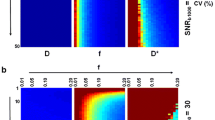

Inadequate blood supply relative to metabolic demand, a haemodynamic condition termed as misery perfusion, often occurs in conjunction with acute ischaemic stroke. Misery perfusion results in adaptive changes in cerebral physiology including increased cerebral blood volume (CBV) and oxygen extraction ratio (OER) to secure substrate supply for the brain. It has been suggested that the presence of misery perfusion may be an indication of reversible ischaemia, thus detection of this condition may have clinical impact in acute stroke imaging. The ability of single spin echo T2 to detect misery perfusion in the rat brain at 1.5 T owing to its sensitivity to blood oxygenation level dependent (BOLD) contrast was studied both theoretically and experimentally. Based on the known physiology of misery perfusion, tissue morphometry and blood relaxation data, T2 behaviour in misery perfusion was simulated. The interpretation of these computations was experimentally assessed by quantifying T2 in a rat model for cerebral misery perfusion. CBF was quantified with the H2 clearance method. A drop of CBF from 58 ± 8 to 17 ± 3 ml/100 g min in the parieto-frontal cortex caused shortening of T2. from 66.9 ± 0.4 to 64.6 ± 0.5 ms. Under these conditions, no change in diffusion MRI was detected. In contrast, the cortex with CBF of 42 ± 7 ml/100 g min showed no change in T2. Computer simulations accurately predicted these T2, responses. The present study shows that the acute drop of CBF by 70% causes a negative BOLD that is readily detectable by T2 MRI at 1.5 T. Thus BOLD may serve as an index of misery perfusion thus revealing viable tissue with increased OER.